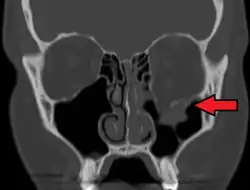

| An orbital blowout fracture of the floor of the left orbit. | |

Thin cut (2-3mm) CT scan with axial and coronal view is the optimal study of choice for orbital fractures.[16][17]